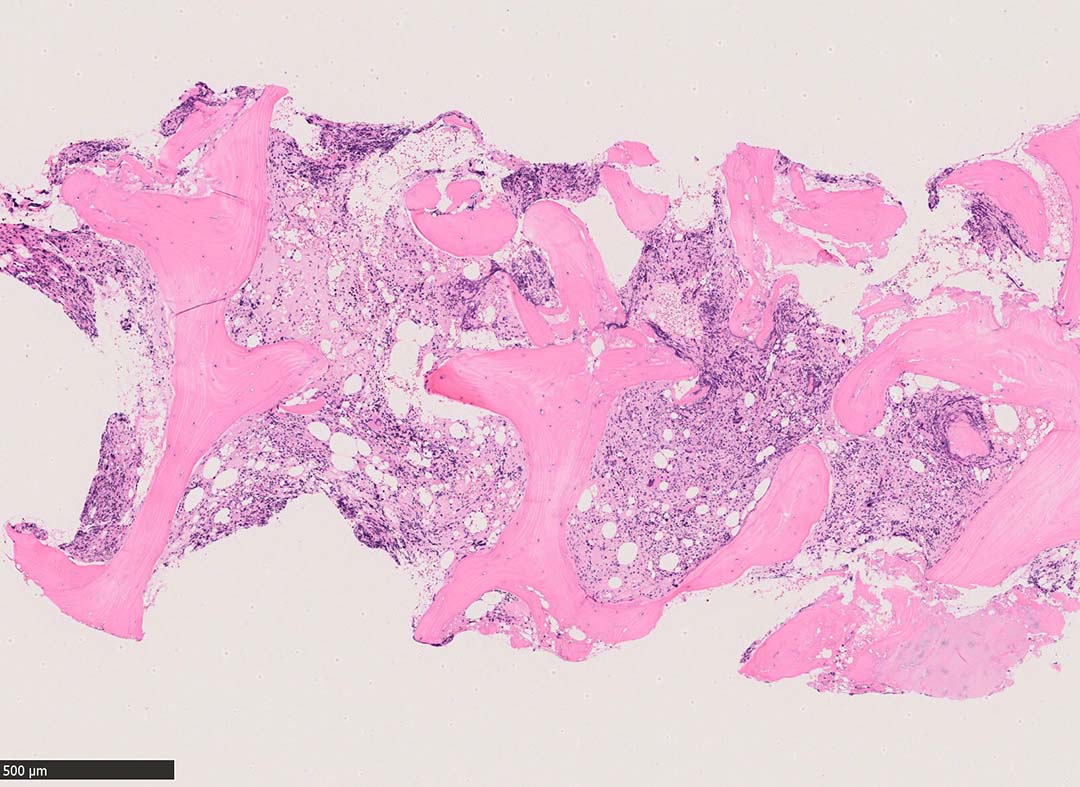

骨髄組織所見 bone marrow biopsy total 6mm in length

Case02; Meylofibrosis, overt fibrosis

77year-old female. 40歳時polycythemia veraと診断されていた.

[注] この症例は詳細は不明であるが, 過去にPVと診断されているため, PVに伴う二次性のmyelofibrosisの診断になる.